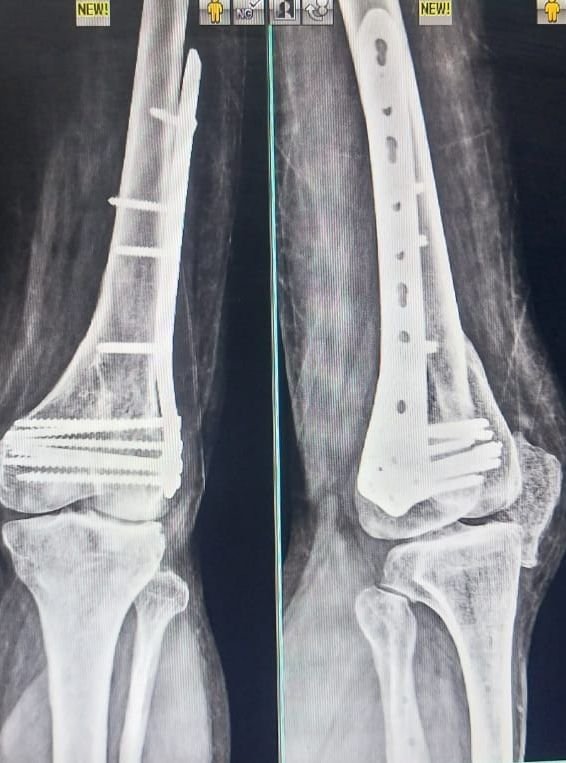

Knee Replacement

Gallery